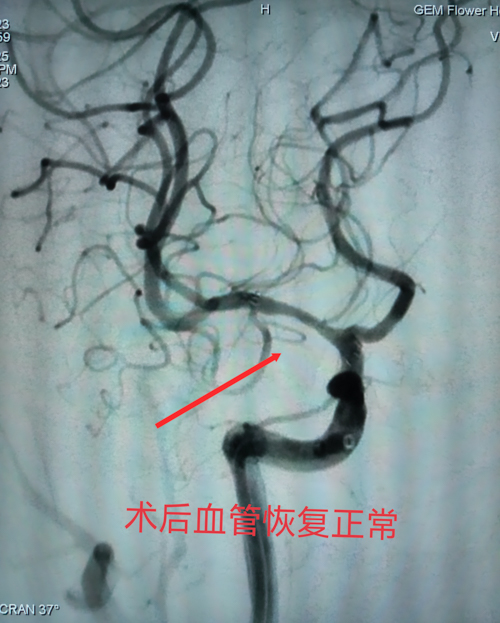

经治愈患者推荐,刘阿姨未等到过完年就慕名来到职业病神经内科。接诊的马磊主任敏锐发现,患者虽多次外院检查均显示:右侧大脑中动脉M1段重度狭窄,但传统药物治疗方案始终未能阻断病情进展。患者血管狭窄率已达95%,血流动力学明显受损,必须尽快进行血管内介入治疗。马主任指着DSA影像向家属解释时,特意用红笔圈出血管拐弯处的狭窄病变,“这个位置就像高速公路的拐角,一旦完全闭塞,将导致灾难性偏瘫。”

经过多学科会诊和周密术前准备,正月十五,手术在介入手术室紧张展开。正如术前预判,患者血管路径异常迂曲,狭窄段位于大脑中动脉分叉远端。“注意微导丝头端塑形角度,保持推进速度......”马主任紧盯显示屏,双手精准操控着细若发丝的介入器械,当脑血管支架完美贴合血管壁时,复查造影显示血流恢复通畅,手术室顿时响起掌声。这类手术堪称“在豆腐上雕花”。